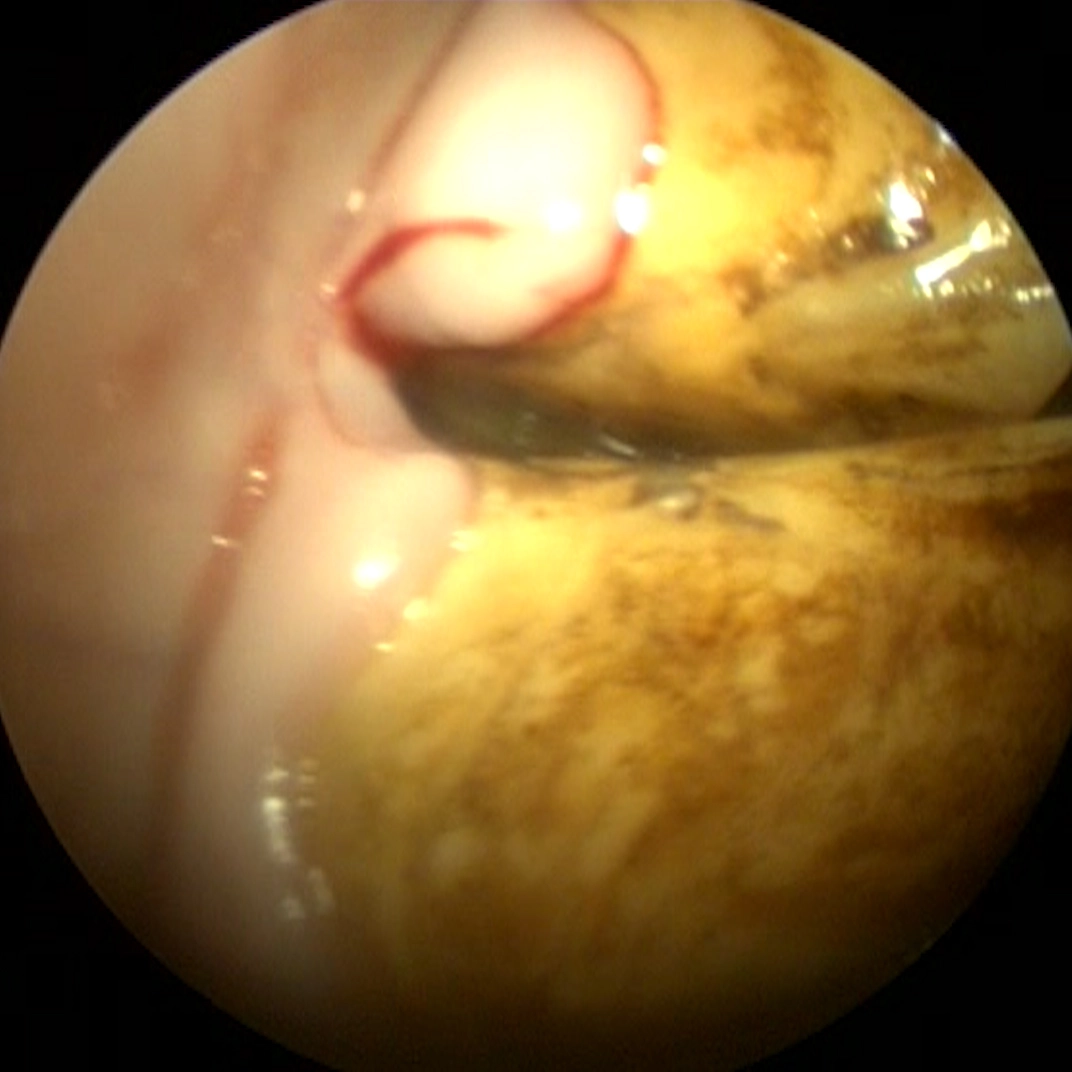

Therapy may involve cleaning the affected area, reshaping tooth surfaces, or corrective dental techniques to reduce food accumulation.

Effective treatment improves comfort, oral hygiene, and long term dental stability.